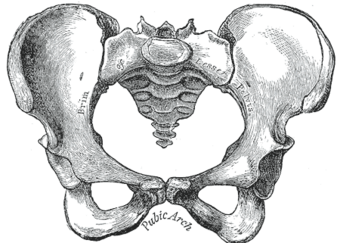

Male type pelvis | |

The principal differences between male and female true and false pelvis include:

- The female pelvis is larger and broader than the male pelvis which is taller, narrower, and more compact.[9] The female pelvis is lighter and thinner than the male pelvis.[10]

- The female inlet is larger and oval in shape, while the male sacral promontory projects further (i.e. the male inlet is more heart-shaped).[9]

- The sides of the male pelvis converge from the inlet to the outlet, whereas the sides of the female pelvis are wider apart.[11]

- The angle between the inferior pubic rami is acute (70 degrees) in men, but obtuse (90–100 degrees) in women. Accordingly, the angle is called subpubic angle in men and pubic arch in women.[9] Additionally, the bones forming the angle/arch are more concave in females but straight in males.[12]

- The distance between the ischia bones is small in males, making the outlet narrow, but large in females, who have a relatively large outlet. The ischial spines and tuberosities are heavier and project farther into the pelvic cavity in males. The greater sciatic notch is wider in females.[12]

- The iliac crests are higher and more pronounced in males, making the male false pelvis deeper and more narrow than in females.[12]

- The male sacrum is long, narrow, more straight, and has a pronounced sacral promontory. The female sacrum is shorter, wider, more curved posteriorly, and has a less pronounced promontory.[12]

- The acetabula are wider apart in females than in males.[12] In males, the acetabulum faces more laterally, while it faces more anteriorly in females. Consequently, when males walk the leg can move forwards and backwards in a single plane. In females, the leg must swing forward and inward, from where the pivoting head of the femur moves the leg back in another plane. This change in the angle of the femoral head gives the female gait its characteristic (i.e. swinging of hips).[13]